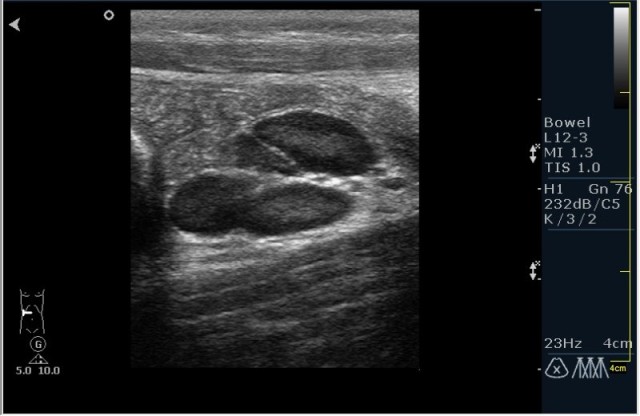

Ребёнок с болями в животе.

инвагинация! :!:

На представленных сонограммах определяется типичная "мишень" или "кокарда" (7ая и 8ая сонограмма сверху), которая при продольном сканировании превращается в "телескоп" (сонограммы 3 & 4). Все это указывет на инвагинацию кишечника (илео-цекальную). Причиной явилось лимфаденопатия брыжейки (которую вы указали). Увеличеные лимфоузлы вместе с инвагинатом хорошо различимы в просвете толстой кишки.

Уважаемые коллеги! Без сомнения имеет место илео-цекальная инвагинация.увеличенные овальные лимфоузлы, да еще такими гроздями характерны для мезаденита.Все зависит от развертывания клинической симптоматики.

duble-buble- intusssusception + lymphadenitis regionale